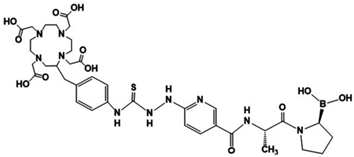

3.2. Chemical Synthesis

3.3. Chemical Evaluation

3.3.1. DOTA-iFAP